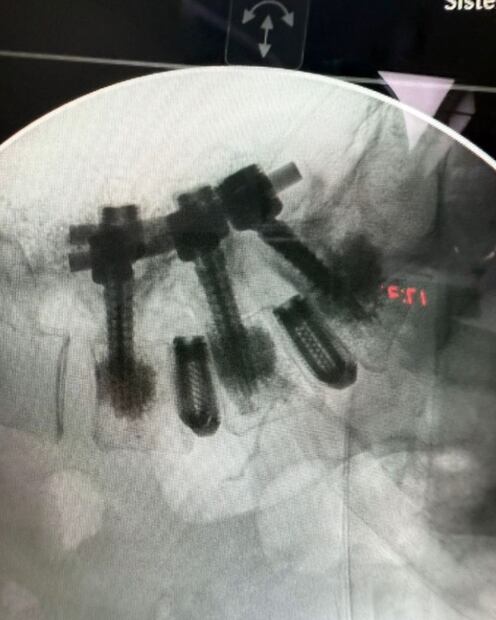

En la foto se ven varios tornillos grandes atravesando múltiples vértebras. Estos tornillos se usan para inmovilizar segmentos de la columna.

Se observa una barra metálica que conecta y estabiliza las vértebras donde se colocaron los tornillos. Algunas partes del implante hacen un ángulo, lo que puede indicar corrección de deformidades o estabilización de fracturas complejas. Este tipo de cirugía se realiza en afecciones severas de la columna como fracturas, escoliosis grave, inestabilidad vertebral, o para tratar ciertos tipos de enfermedades degenerativas o tumores.

El objetivo es proporcionar la máxima estabilidad, facilitar la recuperación o evitar daño neurológico adicional. Por la complejidad del implante, parece una cirugía de columna de alta especialización, probablemente en la zona lumbar o torácica (parte baja o media de la espalda).